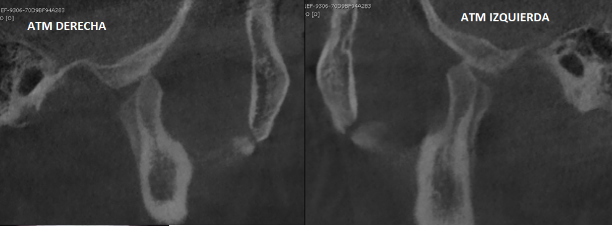

De la misma manera, la tomografía computarizada de macizo facial mostró la mala posición en la que se encontraban los cóndilos mandibulares en relación con sus fosas articulares. No se encontraron zonas hiperdensas circundantes a los cóndilos, por lo que se descartó la probabilidad de anquilosis de ATM (Ver Figura 3).